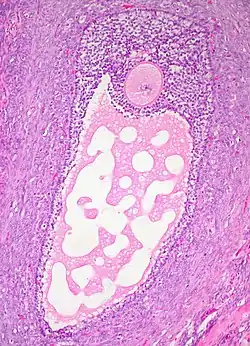

![]() Histology section of a mature ovarian follicle. The oocyte is the large, round, pink-staining cell at top center of the image. | |

Ovarian follicles are the basic units of female reproductive biology. Each of them contains a single oocyte (immature ovum or egg cell). These structures are periodically initiated to grow and develop, culminating in ovulation of usually a single competent oocyte in humans.[5] They also consist of granulosa cells and theca of follicle.

Once a month, one of the ovaries releases a mature egg (ovum), known as an oocyte. The nucleus of such an oocyte is called a germinal vesicle[6] (see picture).